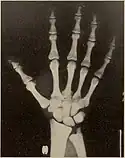

Pycnodysostosis causes the bones to be abnormally dense; the last bones of the fingers (the distal phalanges) to be unusually short; and delays the normal closure of the connections (sutures) of the skull bones in infancy, so that the "soft spot" (fontanelle) on top of the head remains widely open.[9] Because of the bone denseness, those with the syndrome suffer from fractures.[7]

Other abnormalities involve the head and face, teeth, collar bones, skin, and nails. The front and back of the head are prominent. Within the open sutures of the skull, there may be many small bones (called wormian bones). The midface is less full than usual. The nose is prominent. The jaw can be small. The palate is narrow and grooved. There will be delay in fall of milk teeth. The permanent teeth can also be slow to appear. The permanent teeth are commonly irregular and teeth may be missing (hypodontia). The collar bones are often underdeveloped and malformed. The nails are flat, grooved, and dysplastic. High bone density, Acro-osteolysis and obtuse mandibular angle are the characteristic radiological findings of this disorder.[10]

- Hypoplasia or aplasia of the distal phalanges and ribs